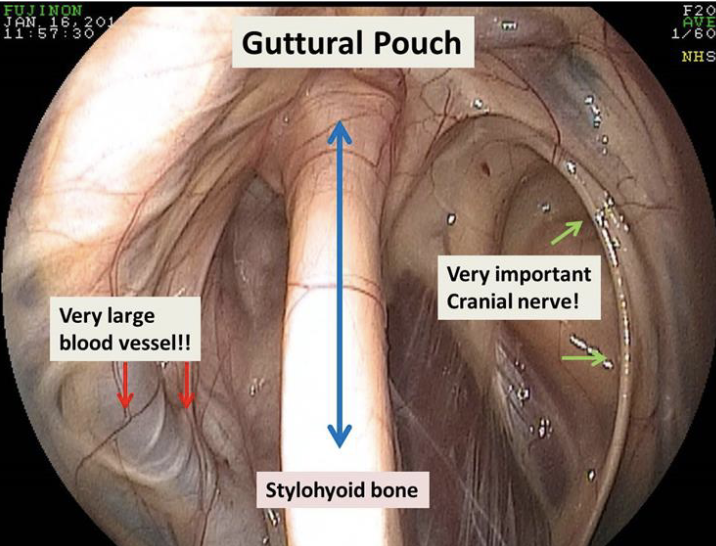

guttural pouch

paired extensions of the eustachian tubes

connects pharynx to middle ear

has various theorized functions

what divides the guttural pouch into medial and lateral compartments

stylohyoid bone

how does the guttural pouch communicate with the pharynx

through the nasopharyngeal orifice of the eustachian tube

this orifice also allows access to guttoral pouch w/ endoscope

what runs in the guttural pouch

external carotid artery (lateral compartment)

cranial nerves 9-12 and internal carotid a. (medial compartment, contained within a fold of mucous membrane on caudal wall)g

guttural pouch mycosis

fungal infxn caused by Aspergillus species

unilateral dz

no predisposition

diphtheritic membrane composed of necrotic tissue, cellular debris, bacteria, and fungal mycelia

can lead to severe & often fatal bilateral epistaxis

guttural pouch cranial nerves cause

9- dysphagia

10- facial paralysis

11- n/a

12- dysphagia